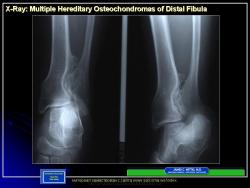

Иллюстрации из литературных источников.